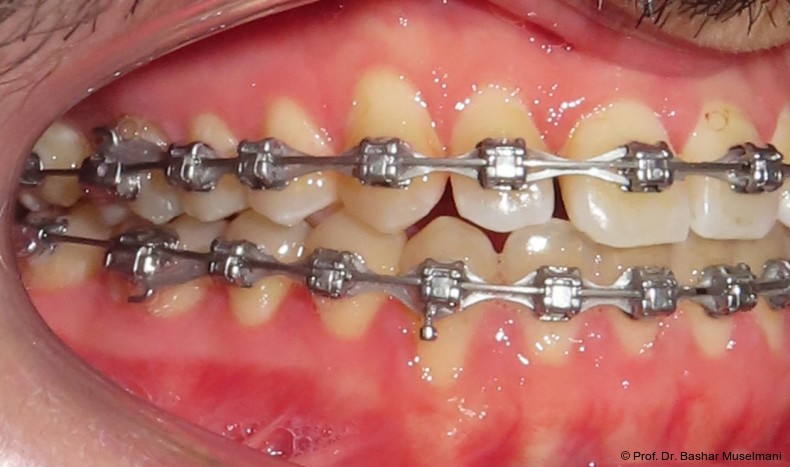

Die Abbildungen 1 bis 3 zeigen die initiale klinische und radiologische Ausgangssituation.

Zur sagittalen Korrektur wurden intermaxilläre Klasse III-Gummizüge eingesetzt.

Diese Sequenz ermöglichte eine schrittweise Ausformung der Zahnbögen, eine kontrollierte Torque-Expression sowie eine präzise Feineinstellung in der Abschlussphase (Abb. 5a–e).

Zwischenbefund

Während des Behandlungsverlaufs wurden ein Kontroll-Fernröntgenseitenbild sowie ein Orthopantomogramm angefertigt.